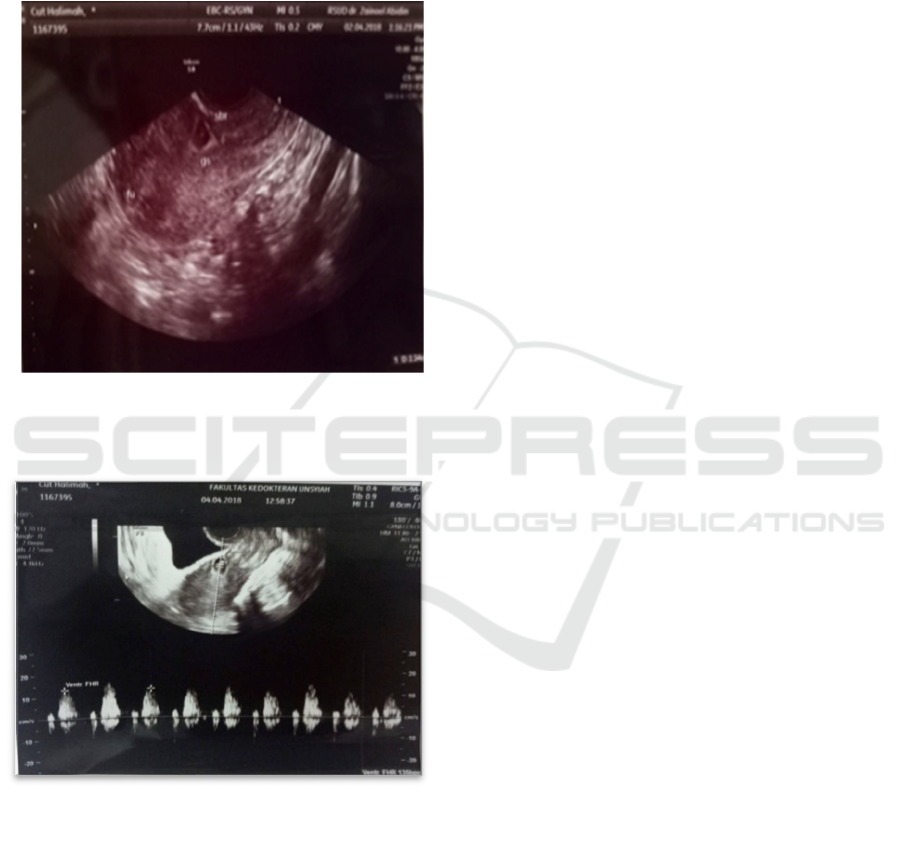

Transvaginal ultrasonography showed uterus was

within normal limit and there was a single

intrauterine gestational sac positioned in the region

lower segment caesarean section. CRL diameter

0,72 mm corresponding to 6-7 wga which is, fetal

pole was present, myometrium thickness 2 mm and

there was no free fluid in the pouch of Dauglas

(Figure 1-2).

Figure 2. Transvaginal ultrasonography showe

d

gestation sac in the lower uterine segment and empt

y

uterine cavity and cervical canal.

Figure 2 Transvaginal ultrasonography showed fetaL

heart rate of the fetus.